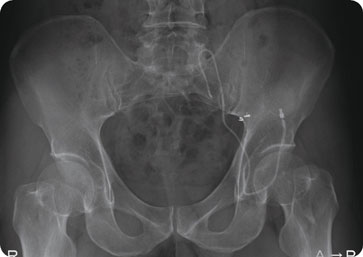

図1

図1 動脈内カテーテル設置とリザーバー接続

腫瘍が偏側性の場合には、腫瘍側の大腿動脈 をセルジンガー法で骨盤動脈造影を行い、薬剤 を多く腫瘍側に流入させるため、大臀動脈をコ イルで塞栓して、血流改変を行う。アンスロン カテーテルを内腸骨動脈に設置する。

次いで、ソケイ部でカテーテルをループ状に して、腸骨稜あたりの皮下組織にリザーバーを 埋め込んで、カテーテルと接続する。あぐらを かいてもカテーテルが屈曲しないように考案した。腫瘍が多発性の場合にはカテーテルを腹部 大動脈分岐部直上に設置して、動注時には両側 大腿動脈を用手的に圧迫して、リザーバーから 薬剤を注入した。